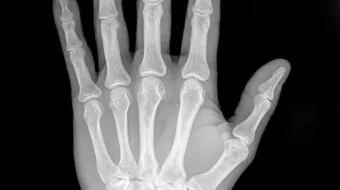

واستطاع رونتغن اكتشاف أشعّة إكس في عام 1895م، حين كان يجري تجربة تدفُّق التيّار الكهربائيّ في أنبوب زجاجيّ مُفرغ جزئيّاً من الهواء، وهو أنبوب أشعّة الكاثود؛ حيث لاحظ أنّ هناك ضوءاً قد نتجَ عن قطعة قريبة من البلاتين، وذلك عند تشغيل الأنبوب، فخرجَ بنظريّة، وهي أنّه عند اصطدام الإلكترونات (أشعّة الكاثود) بجدار الأنبوب الزجاجيّ، تظهرُ أشعّة مجهولة تُسبِّب وميضاً عند اصطدامها بالمادّة، ومن خلال عدّة ملاحظات، اكتشف أنّ هذا النوع من الأشعّة شفّاف لبعض الموادّ، مثل: الخشب، والورق، والألومنيوم، كما أنّ له تأثيراً في لوحات التصوير الفوتوغرافيّ، وهو لا يحمل أيّة خاصّية من خصائص الضوء، مثل: الانعكاس، أو الانكسار، ونتيجة لهذا، اعتقد بشكل خاطئ أنّه لا علاقة لهذا النوع من الأشعّة بالضوء، ونظراً لطبيعة هذه الأشعّة المجهولة، فقد أطلق عليها اسم أشعّة إكس، حيث التقطَ أوّل صورة باستخدام هذه الأشعّة لعظام يد زوجته.[3]

بسبب مقدرة أشعّة إكس على اختراق موادّ مُعيَّنة، يتمّ استخدامها في عمليّات التفتيش الأمنيّ، وعند نَقْل البضائع والركّاب؛ حيث تسمحُ هذه الأشعّة، ومن خلال أجهزة الكَشْف عن الصور الإلكترونيّة، بتصوير محتويات الحقائب، والأمتعة، كما أنّها تُستخدَم في تصوير العِظام، وهي تُستخدَم كطريقة غير مُؤلِمة؛ لتشخيص المرض، ومراقبة العلاج، إضافة إلى أنّها تساعد في دَعْم العاملين في المجال الطبّي عند إدخالهم دعامات، أو أيّة أجهزة داخل الجسم، كما أنّ لها دوراً في علاج الأورام، وإزالة الانسدادات، والجلطات الدمويّة؛ وذلك لأنّ أشعّة إكس المُؤينة تُرسِّب كمّيات كبيرة من الطاقة في منطقة صغيرة؛ إذ تُجرِّد هذه الطاقة الإلكترونات من الذرّات، وهذا يؤدّي إلى تغيُّر في خصائصها الكيميائيّة، وكَسْرٍ للروابط الجزيئيّة، وبالتالي تَلَف الخلايا، أمّا إذا تمّ توجيهها إلى الخلايا السرطانيّة، فإنّها سوف تقتلها.[1]